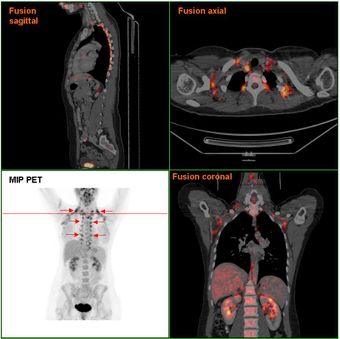

النسيج الشحمي الأسمر لدى إمرأة تجري فحص PET/CT exam | |